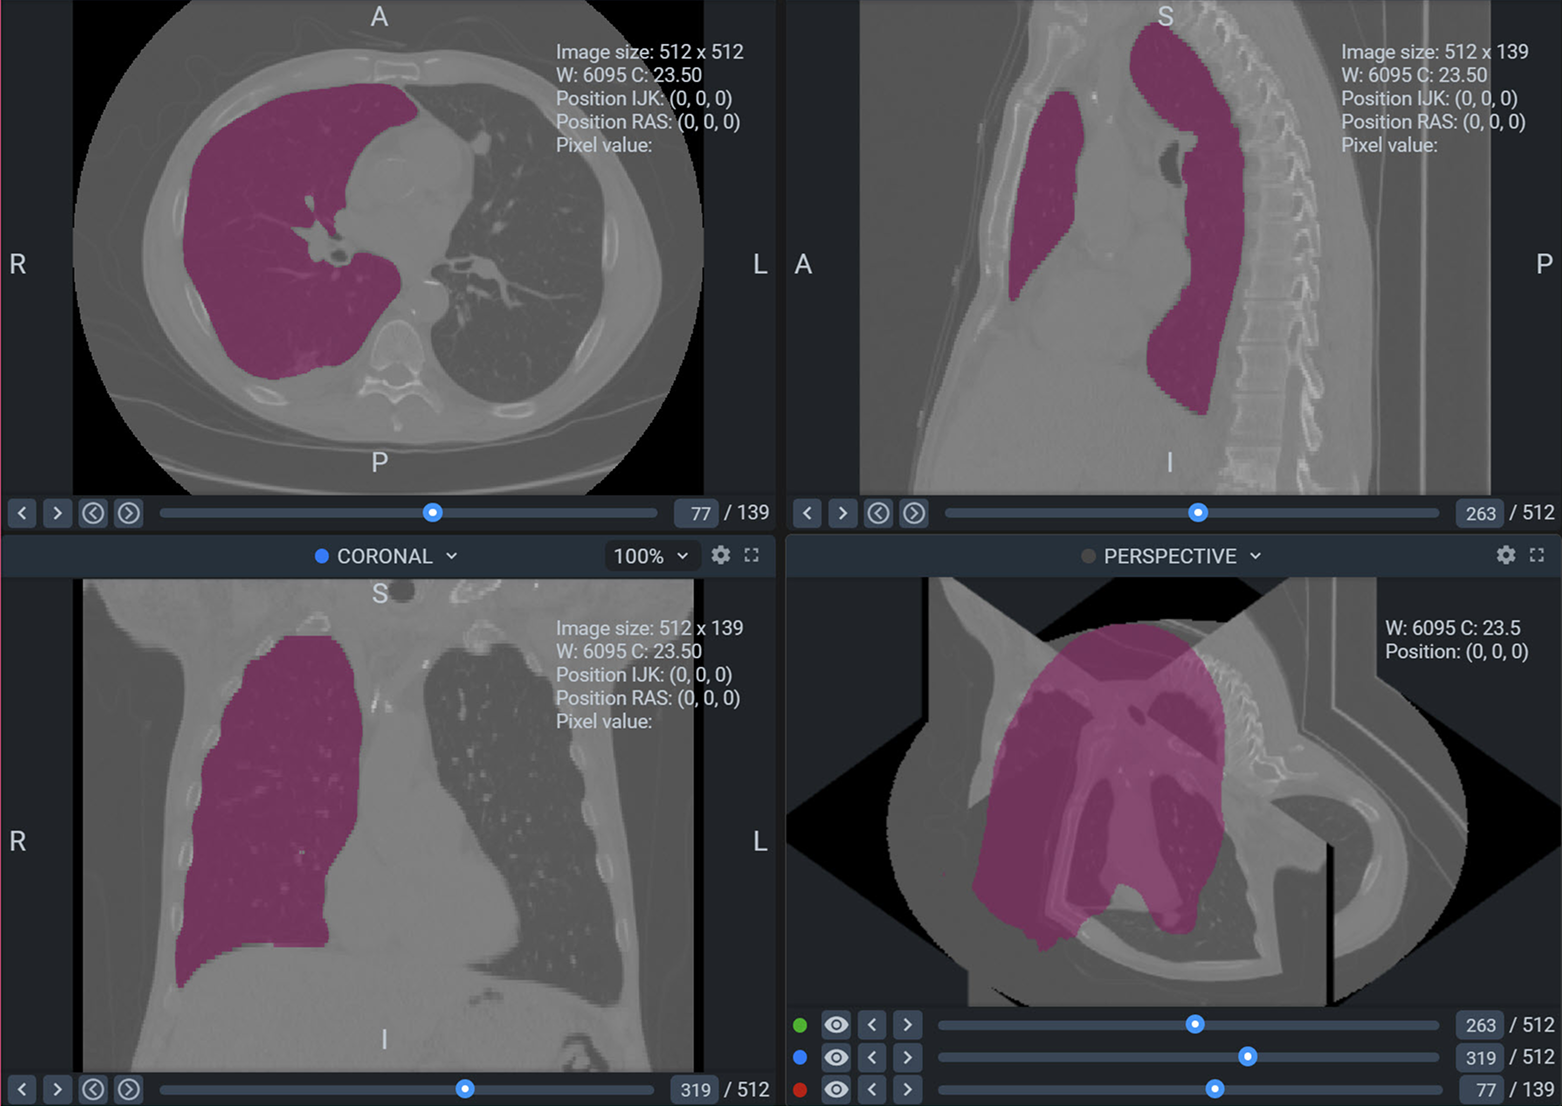

Medical image annotation is the process of labeling medical images, such as X-rays, MRIs, CT scans, and ultrasound images, to help AI models recognize patterns and abnormalities. This process involves trained radiologists, pathologists, and data annotators who precisely mark anatomical structures, tumors, and other critical elements within medical images.

1. Segmentation Annotation

- Identifies and labels different regions within a medical image, such as tumors, organs, and tissues.

- Used in oncology, cardiology, and neurology for precise diagnosis.

5. 3D Image Annotation

- Used for volumetric scans like MRI and CT to analyze structures in three dimensions.

- Enhances AI capabilities in complex medical imaging.